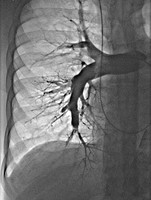

Uniwersyteckie Centrum Kliniczne, szpital Gdańskiego Uniwersytetu Medycznego dołączyło do wąskiego grona ośrodków kardiologicznych w Polsce wykonujących balonoplastyki tętnic płucnych (BPA) u pacjentów z zakrzepowo-zatorowym nadciśnieniem płucnym. Tym samym zainicjowano program inwazyjnego leczenia tej rzadkiej choroby w Klinicznym Centrum Kardiologii UCK kierowanym przez prof. Grzegorza Raczaka. Pierwszy zabieg wykonał zespół w składzie: dr Dariusz Ciećwierz i dr Grzegorz Żuk pod nadzorem prof. Marcina Kurzyny z Europejskiego Centrum Zdrowia w Otwocku, który jest pionierem tych zabiegów w naszym kraju.

Zakrzepowo-zatorowe nadciśnienie płucne to stosunkowo rzadkie powikłanie ostrej zatorowości płucnej. Zgodnie z aktualnymi wytycznymi Europejskiego Towarzystwa Kardiologicznego podstawową metodą leczenia inwazyjnego tych chorych jest operacja kardiochirurgiczna. Jednak leczenie przezskórne w postaci BPA zyskuje coraz bardziej na znaczeniu. Obecnie wykonuje się je u pacjentów, którzy zostali zdyskwalifikowani z leczenia kardiochirurgicznego lub u chorych po leczeniu operacyjnym, u których nie uzyskano optymalnego efektu leczenia.

Leczenie inwazyjne w postaci BPA to leczenie wieloetapowe rozłożone u każdego pacjenta na kilka sesji zależnie od lokalizacji zmian w krążeniu płucnym i wyników cewnikowania serca. Efekty, które udaje się uzyskać na podstawie doświadczeń innych ośrodków pozwalają na istotną poprawę wydolności fizycznej pacjentów i normalizację parametrów hemodynamicznych.